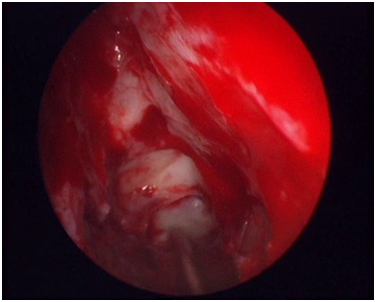

After preparing the bed (Figure 5) it is the time to receive the graft. We have already estimated the surface we need to cover by studying the CT. Usually a graft with dimensions 5x5cm will suffice. The thickness of the graft has also been already estimated at 0.15mm. The graft must be thin enough to contain only a thin slice of dermis. The optimal area for receiving the graft is the thigh, preferably its inner surface. We take the graft from the ipsilateral leg by the use of an electric dermatome. Prior to insertion, the graft must be trimmed to acquire the proper contour. Also, multiple cuts are performed on its surface so as to prevent air and blood clots to accumulate between the graft and its bed. Furthermore, these cuts will allow small remnants of mucosa to find their way into the nasal cavity preventing the formation of mucocele (Figure 6). After completing trimming, the graft is wrapped around a sterile paper and is inserted inside the nose (Figure 7). After the insertion of the graft no further actions must be taken inside this nostril. No packing of any kind must be inserted. The graft remains in its position due to viscosity rather than any other supporting force.

Figure 6 Trimming the graft.